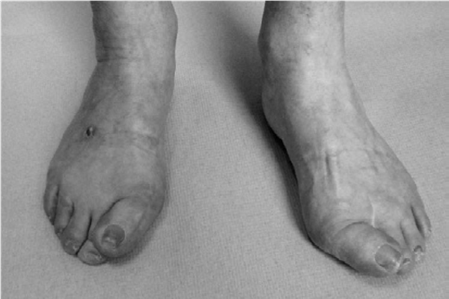

Foot and ankle structured oral questions5: Acquired adult flatfoot EXAMINER : I would like you to look at thi…